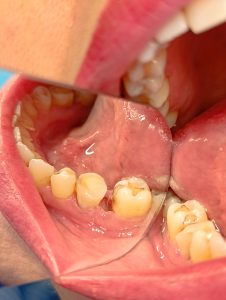

Η ασθενής επισκέφτηκε το ιατρείο γιατί είχε φοβερό πόνο στη δεξιά πλευρά της κάτω γνάθου. Μετά την κλινική και ακτινογραφική εξέταση διαπιστώθηκε η παρουσία ενός νεογιλού ακόμη δοντιού στο στόμα της. Δυστυχώς το νεογιλό δόντι είχε σπάσει στα δύο. Σα λύση θεραπείας δόθηκε η διχοτόμηση του νεογιλού δοντιού και στη συνέχεια η ανασύσταση του με σύνθετη ρητίνη. Κατά τη διαδικασία της διχοτόμησης χορηγήθηκε στην ασθενή τοπική αναισθησία και στη συνέχεια οι ρίζες του δοντιού χωρίστηκαν και αφαιρέθηκε εκείνη η ρίζα που είχε σπάσει. Η ασθενής δεν αισθάνθηκε καθόλου πόνο. Σε επόμενο ραντεβού ανασυστάθηκε το δόντι. Η συγκεκριμένη θεραπεία ήταν μια λύση ανάγκης, καθώς η ασθενής δεν ήθελε να τοποθετήσει εμφύτευμα στο στόμα της (η οποία αποτελούσε την εναλλακτική θεραπεία).

Σίγουρα με τις παρούσες συνθήκες δεν μπορούσε να αποδοθεί σημείο επαφής με το διπλανό δόντι, καθώς η απόσταση ήταν αρκετά μεγάλη.

Η ασθενής είναι χαρούμενη που απέφυγε τη διαδικασία του εμφυτεύματος και μέσα σε μία συνεδρία της δόθηκε λύση στο πρόβλημά της.

Αρχική εικόνα πριν τη διχοτόμηση του δοντιού